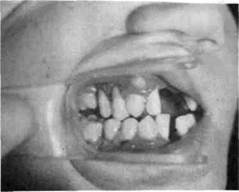

Хронический катаральный гингивит может возникнуть не только вследствие микробного налета, но и других местных причин — дефектов пломбирования и ортодонтического лечения, аномалий прикуса, прикрепления уздечек и тяжей слизистой оболочки, коротких уздечек губ, мелкого преддверия полости

рта, кариозных полостей придесне-вой локализации, изменения состава и уменьшения количества ротовой жидкости, а также различных видов травм (рис. 8.1).

Рис. 8.1. Хронический катаральный гингивит.